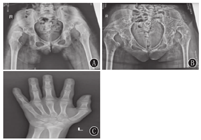

血尿便常规、血生化、甲状腺功能、脑脊液、胸片、心电图、肝胆胰脾+双肾上腺B超、染色体核型、尿有机酸分析及血氨基酸、肉碱和琥珀酰丙酮检验均无异常。雌二醇、孕酮、睾酮、催乳素、促卵泡生成素、促黄体生成激素均正常;血清极长链脂肪酸(VLCFA)正常。肌电图:多发性周围神经源性损害肌电改变(主要累及感觉、运动神经脱髓鞘)。听觉诱发电位:重度双侧感音神经性听力损失;先证者脑电图:异常儿童脑电图(背景活动减慢);其姐脑电图:正常青少年脑电图;先证者8岁头颅MRI:小脑脑沟宽深。其姐14岁头颅MRI:双侧小脑半球萎缩(图1)。先证者左腕关节正位片(骨龄片)正常。其姐14岁骨龄片:8枚腕骨发育,相当于10~11岁(图2)。先证者双肾B超正常;其姐双肾B超:双肾形态略小(左肾88 mm×39 mm,右肾85 mm×36 mm)。其姐14岁子宫附件B超:子宫形态小,宫体长经20 mm,前后径7 mm,横经10 mm,双侧卵巢显示不清(图3)。

DBPD是一种罕见的过氧化物酶体单个酶缺陷遗传病[2]。1989年由Watkins等[15]首次描述;1997年明确HSD17B4为其致病基因[16] 。本病以新生儿脑病、多发性神经病、精神运动发育障碍、双侧感音神经性听力损失、肝大、多发畸形为临床特征。目前还发现其他的临床表型,如卵巢功能障碍、小脑功能障碍、运动退化、骨成熟延迟、骨骼畸形等[1,3,4,6,7,8,9,11,17]。本组2例患儿为同胞姐弟,相同表型为新生儿癫痫发作、肌无力、精神运动发育迟缓、共济失调、足部畸形;姐姐还合并卵巢功能障碍、骨骼发育异常。临床电生理表现为双侧感音神经性听力损失、多发性周围神经病变。颅脑MRI示小脑萎缩,符合DBPD的诊断。患儿血清VLCFA正常,推测原因为酶活性残留。2例患儿严重程度有差异,推测原因为存在不同的酶活性残留量。